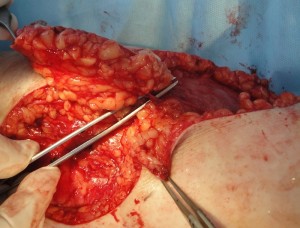

Проведено широкое иссечение новообразования в пределах неизмененных тканей радиоволновым методом Surgitron, гемостаз. В область дна раневого дефекта, размерами 10 х 9 см. предлежит большеберцовая кость, что является показанием к закрытию раны васкуляризированным лоскутом (Рис. 8А). После дессекции и выделения намеченный лоскут поднят, проведена визуализация перфорантов формирующих питающую ножку PPPF (Рис 8Б). Сам лоскут ротирован аксиллярно на 180 град. (Рис 8В), где адаптирован к краям раневого дефекта и фиксирован узловыми швами.1 Рана в реципиентной зоне сопоставлена с кожными краями лоскута и ушита, дефект донорской зоны закрыт путем сближения краев и наложением линейного шва. При этом важным моментом является соблюдение основного принципа пластической хирургии – ушивание раны без натяжения кожи. Послеоперационное течение гладкое. После заживления ран и верификации диагноза в гистологической лаборатории пациентка выписана к труду на 27 сутки после операции. После удаления обширного новообразования на голени путем пластики PPPF сформирован устойчивый кожный покров, максимально близкий по структуре и цвету утраченному вследствие заболевания, без значительного нарушения контуров конечности как в донорской, так и в реципиентной зоне. Пациентка полностью удовлетворена результатом лечения (Рис 8Г).

Рис. 8. А – цифровое фото раневого дефекта на голени после иссечения новообразования.

Б – вид поднятого после дессекции лоскута, визуализация перфорантов, формирующих питающую ножку. В – вид лоскута после аксилярной ротации и адаптации в реципиентную зону раневого дефекта. Г – цифровое фото голени в раннем послеоперационном периоде, после снятия швов и перед выпиской из клиники. Отмечается адекватное восстановление кожного покрова без нарушения контуров конечности, как в донорской, так и в реципиентной зоне. Д – отдаленный результат, через 20 месяцев после операции; рецидива заболевания нет, пациент полностью удовлетворен состоянием кожного покрова, контуром голени и функцией нижней конечности.